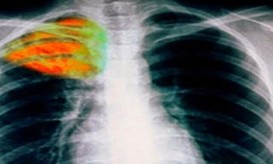

Φυματίωση: Ραγδαία αύξηση στα κρούσματα που δηλώνονται κάθε χρόνο στην Ελλάδα

Έφτασαν στα επίπεδα του 2014. Τι άλλαξε μετά την πανδημία, σύμφωνα με τα υπάρχοντα στοιχεία.

Μετά την πανδημία καταγράφεται σημαντική αύξηση στις μεταδοτικότερες μορφές φυματίωσης, προειδοποιεί.